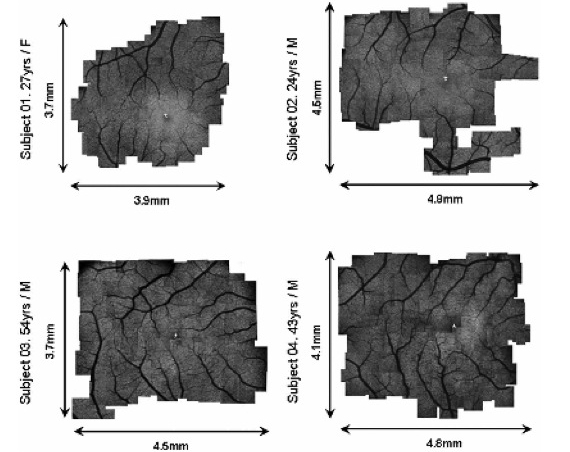

One method for wide-field AO imaging relies on the use of a scanning mirror. The individual AO corrected images are small, but a series of images is recorded and are then stitched together to yield one large, high-resolution image. The images in Fig. 3 are wide. This method is simple and efficient, but it encounters practical limitations. An imaging session lasts typically one hour and this excludes the examination of young patients. Also, the reconstruction of a large image from a series of small images is not straightforward: ideally, the patient’s visual fixation should be perfectly steady over all acquisitions. Large variations in the fixation lead to artifacts in the image reconstruction. This is a particular difficulty for patients with visual impairment, but variations occur even in healthy eyes, when the subject is trying to maintain a steady fixation.